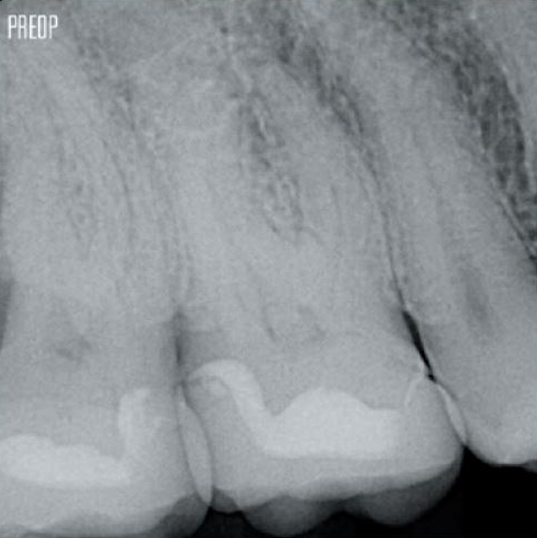

Un tratamiento exitoso de conducto radicular comienza con un acceso adecuado a la cámara pulpar. El procedimiento ideal proporciona acceso a la entrada del conducto radicular con una pérdida mínima de dentina.

Se recomienda utilizar una cavidad endodóntica conservadora (Conservative Endodontic Cavity, CEC) con el sistema TruNatomy®.

Ahora el acceso es posible desde diferentes ángulos mientras que, anteriormente, había que sacrificar la estructura (cavidad endodóntica tradicional).1

No es necesario el acceso en línea recta.1

Fotos cortesía del Dr. Ahmed Salman